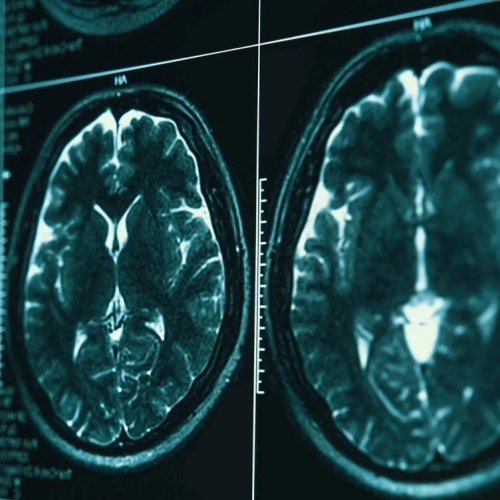

Tau蛋白病是一类以Tau蛋白异常沉积为主要病理特征的神经系统疾病。其中最为人熟知的代表是阿尔茨海默病,此外还包括额颞叶痴呆等疾病。

在正常情况下,Tau蛋白有助于维持神经细胞内微管结构的稳定。但在疾病状态下,Tau蛋白发生异常磷酸化并聚集成团,形成细胞内沉积物。这些异常聚集体会: